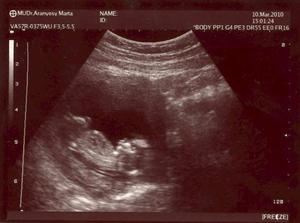

- 7.4.2010 kontrola u Dr.G (17+3tt) splněno, co se nám to v bříšku vyklubalo to ještě nevíme, bejbátko bylo poněkud hyperaktivní a ani chviličku nepoleželo

- 27.4.2010 velký UTZ v nemocnici - ten máme za sebou, avšak pořád nevíme co to bude, páč naše malá prdelka měla mezi nožkama pupečníkovou šňůru